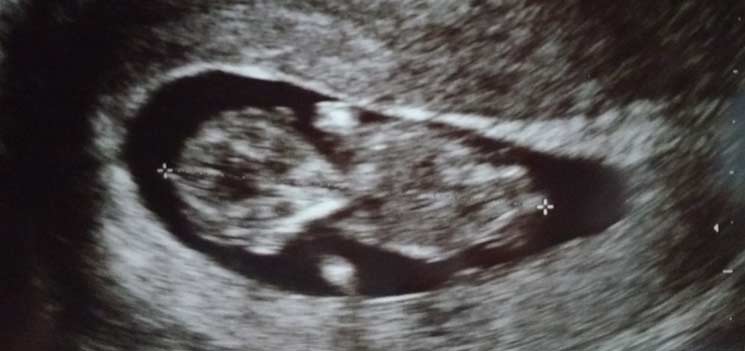

Stimmungsschwankungen - Tagebücher aus der Schwangerschaft von Rena aus Neuss